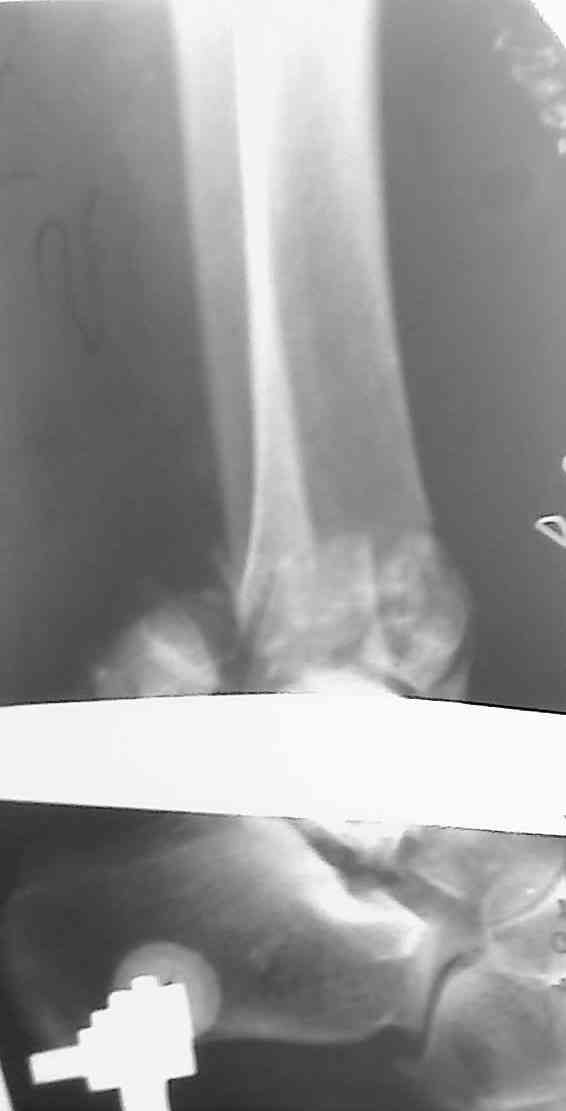

Добавлены КТ снимки. Прошу прощения за качество.

С уважением, Коваленко А.Н.